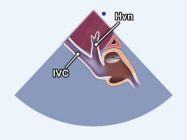

Cửa sổ siêu âm dưới sườn

Ghi hình tĩnh mạch chủ dưới Cắt theo trục dọc của cơ thể người bệnh |

Tĩnh mạch chủ dước (IVC) cắt dọc | |||||

| 2.26. Mặt cắt dưới sườn ghi hình tĩnh mạch gan (video 67) |

||||||||

|

|

Cửa sổ siêu âm dưới sườn

Từ mặt cắt tĩnh mạch chủ dưới, nghiêng nhẹ đầu dò sang phải và ngả đầu dò lên trên. |

Tĩnh mạch chủ dưới (IVC) và tĩnh mạch gan (Hvn) | |||||